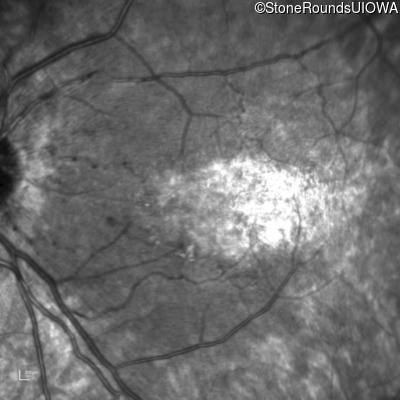

Infrared Fundus Photograph - Right - 20/160

Exemplar

Infrared Fundus Photograph - Left - 20/80 -1